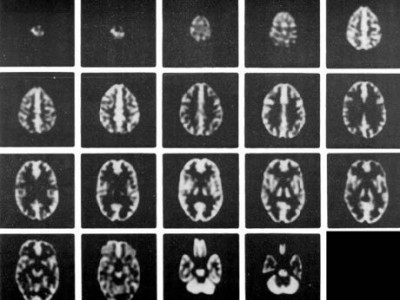

-在脑部SPECT及脑部PET的研究中,从解刨学角度精确的模拟放射性分布;在MRI研究中,精确模拟质子密度及驰豫参数打的分布

Anatomically accurate simulation of radioactivity distribution for brain SPECT and brain PET studies* and distribution of proton density and relaxation parameters for brain MRI studies

-在血流和代谢研究中模拟正常灰质和白质的4:1摄取率(按部分体积效应模拟)

Simulates 4:1 uptake ratio (by partial volume effect) seen for normal gray and white matter in flow and metabolic studies